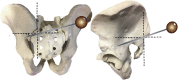

Sacropelvic is a complex junctional area owing to the complex regional anatomy and higher biomechanical stress. However extension of construct is indicated in cases with complex deformities, high grade spondylolisthesis, and complex fractures. The challenges remain which includes pseudoarthrosis and fixation failures. The fixation techniques have constantly evolved over time with better results with iliac screws and S2-alar-iliac screws. This article gives background on evolution, biomechanics, and recent update of use of robotics for sacropelvic fixation.